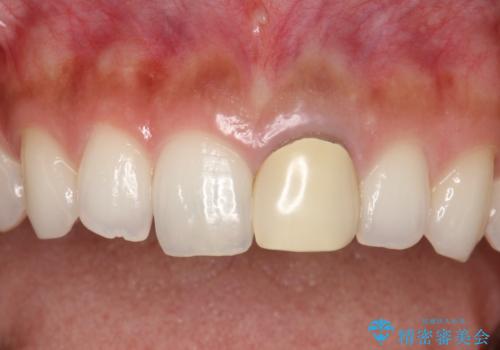

- 以前装着された前歯のかぶせ物の色を変えたいとのことで来院されました。

土台からの再治療を行い、オールセラミッククラウンを装着する治療計画としました。

保険適用のかぶせ物は天然の歯のような色見を表現するのは難しいといえます。

自然な歯をご希望な場合、金属を使わないオールセラミックがおすすめです。